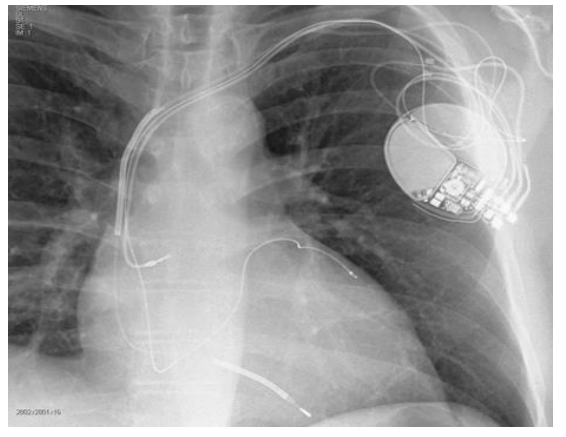

No contexto de pacientes com insuficiência cardíaca, assinale o

caso descrito a seguir que teria maior benefício de receber o

dispositivo observado na radiografia a seguir.

Abreviaturas: BRD: Bloqueio de ramo direito / BRE: Bloqueio de ramo esquerdo / FE: Fração de ejeção / IC: Insuficiência cardíaca / NYHA: New York Heart Association.